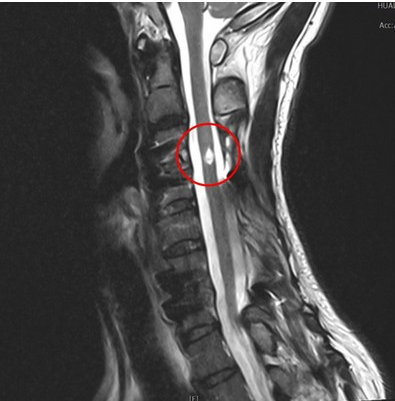

右圖:紅圈為邱先生頸椎脊髓損傷處。邱先生表示,透過電刺激器協助他站立時的穩定性,再搭配高強度的手腳肌力、平衡感、耐力復健,現在已經可以獨自一人自由行動,大大提升了生活品質與工作效率。

五十五歲的邱先生,四年前因一次衝浪活動遇到「瘋狗浪」撞上岩石,造成頸椎第五節嚴重損傷合併四肢癱瘓,接受頸椎減壓手術後固定後持續復健,雖然可以靠著手杖支撐走動,但因左腳明顯無力,且行走約二十分鐘就感覺體力耗盡,只能坐著或躺著休息。二○二○年五月間到花蓮探望親人,得知花蓮慈院推動中西醫復健合療,包括使用內生性幹細胞療法(G-CSF)、針灸、復健機器人等,已累積許多經驗,幫助腦傷、脊髓損傷的病人找到「能醒能走」的希望,便到了林欣榮院長的門診求治,先接受內生性幹細胞療法後,再轉介到了蔡昇宗主任的門診接受脊髓電刺激治療。